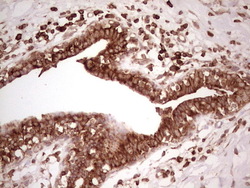

Supportive validation

- Submitted by

- OriGene (provider)

- Main image

- Experimental details

- Immunohistochemical staining of paraffin-embedded Adenocarcinoma of Human breast tissue using anti-WIBG mouse monoclonal antibody. (Heat-induced epitope retrieval by 1 mM EDTA in 10mM Tris, pH8.5, 120C for 3min, TA806496)

- Validation comment

- IHC